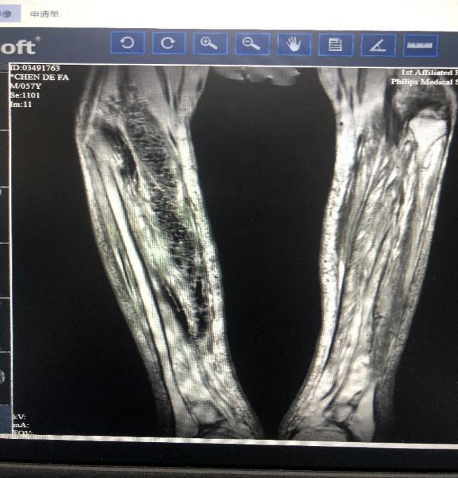

5月8日双下肢血管彩超:1.双下肢动脉内中膜不均增厚改变并多发斑块形成。2.左侧比目鱼肌肌间静脉血栓形成。3.双下肢皮下软组织层水肿(图4)。

图4 双下肢影像结果